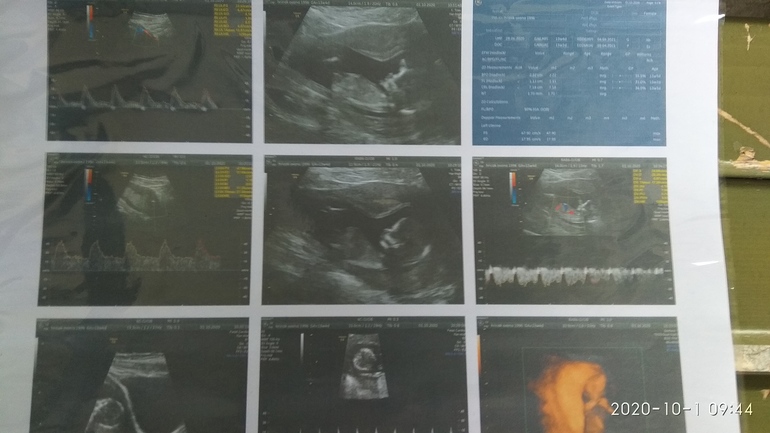

На кого похожа кроха? ❤️ Или 💙? На узи предположили мальчика😍

Пол малышаА я совсем не пойму. Муж очень хочет сына, но очень давно гадалка сказала ему что будет дочь😁 вот мы и ждали дочь🤷 срок 13+4 на момент узи

По фото не знаю. Но мне на скрининге первом хороший узист мальчика сказал. Причем как то очень уверенно и как видите прав оказался

Да мне тоже так уверенно)) я ещё спрашиваю "точно?" 😂😂😂 А она такая "да, похоже"

Мальчик) Хотя возможно то, что я вижу это не половой бугорок, тогда не понятно)

А Вам узист сделала предположение? Я делала скрининг в 11+4 недели, потом были проблемы и ходила на узи в 13+1, так вот в 11 недель половой бугорок был опущен, а в 13 недель хорошо так поднят)) Я сначала была уверена что девочка, а после 13 недель поняла что мальчик) У Вас тоже 13 недель, думаю если мальчик половой бугорок уже наверно хорошо поднят)

Я же в заголовке написала)) предположили мальчика) Тоже так думаю, срок то не 12 недель, а уже почти 14. Ошибиться вряд-ли могла. Тем более в платной клинике - вообще бы не говорила, если не понятно.

Здесь не видно половой бугорок... Чуть левее бы кадр сдвинуть.

Блин) а я думала это что-то там торчит)

Ну, на этом сроке они похожи, и торчит что у девочек, что у мальчиков 😊 Важен наклон)) На фотке виднеется, вроде как, что-то похожее на бугорок, но это может быть просто искажение УЗИ, почётче бы. Не знаю, может, другие разглядят лучше. По мне, немного сместить бы влево, чтобы точно понимать.

Узистка аж три раза фоткала - так и не словила))) стесняшка, значит может и девочка😊